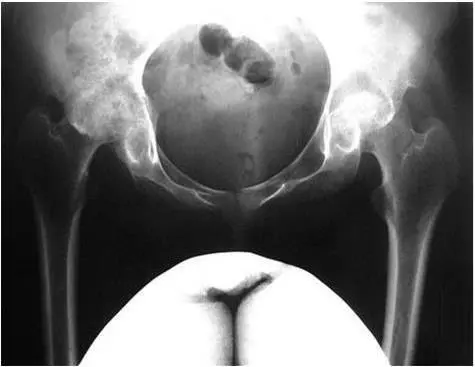

Рис 23 Асептический некроз головок бедренных костей В ряде случаев - фото 11

Рис. 2.3. Асептический некроз головок бедренных костей

В ряде случаев развиваются интенсивные боли в тазобедренных суставах. Они, как правило, обусловлены развитием асептического некроза головок бедренных костей (рис. 2.3).